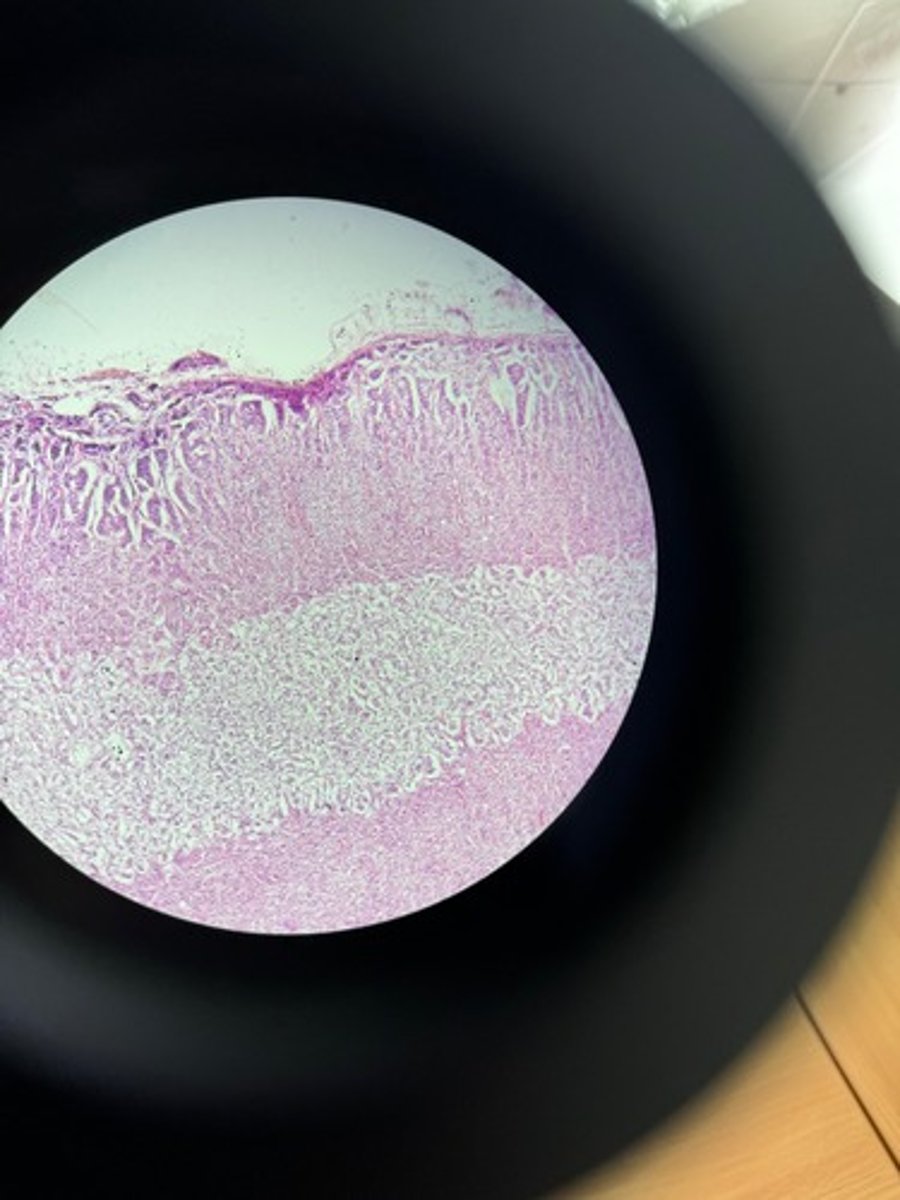

Thyroid gland HE

Thyroid gland HE

Thyroid gland HE

Thyroid HE